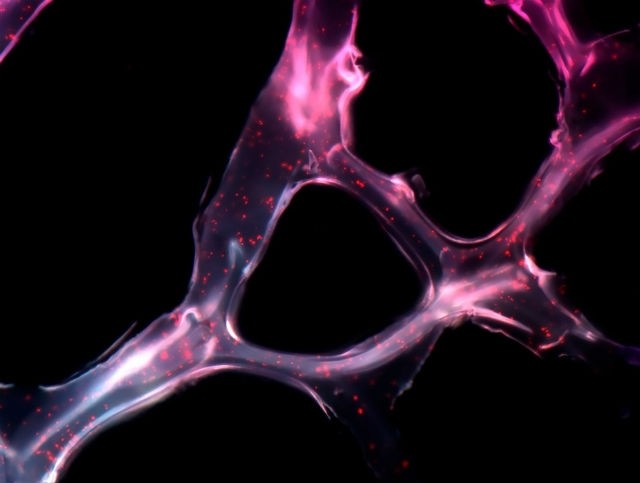

Cáncer de ovario. (Foto: Wellcome collection)